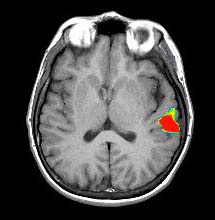

Verbal Comprehension

Right-handed volunteer, 32 year-old-man |

ON: Listening to a story

OFF: Concentrate on the back ground noise |

| T-Test |

0.0001 |

3.8 |

| Activation |

Left hemisphere activation is clearly greater. The activation is in the following areas: Broca's (image 5), Wernike's (images 4 and 5), left supramarginal gyrus (heteromodal associative area, in image 5), left motor and premotor strip. The primary auditory areas are also activated predominantly on the left. |